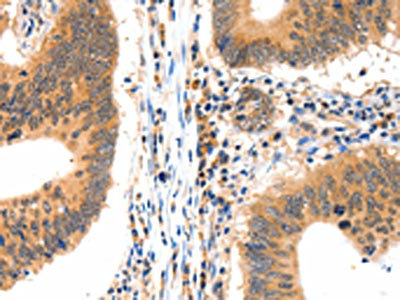

The image on the left is immunohistochemistry of paraffin-embedded Human colon cancer tissue using CSB-PA163355(LRPPRC Antibody) at dilution 1/15, on the right is treated with synthetic peptide. (Original magnification: ×200)

The image on the left is immunohistochemistry of paraffin-embedded Human ovarian cancer tissue using CSB-PA163355(LRPPRC Antibody) at dilution 1/15, on the right is treated with synthetic peptide. (Original magnification: ×200)